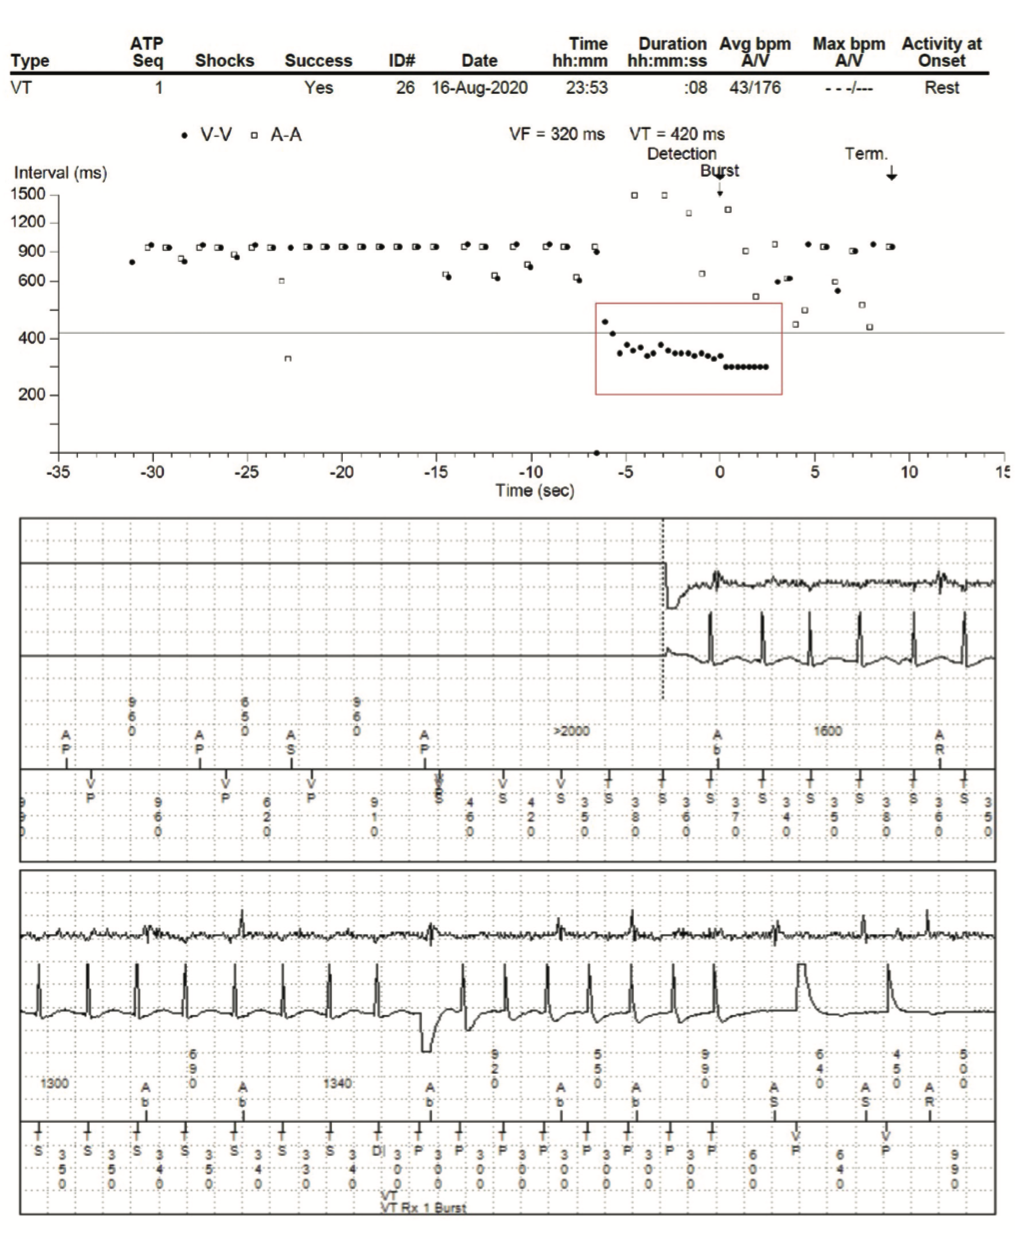

Since initial device implantation, the patient has needed a total of 6 implantable devices—2 pacemakers and 4 ICDs—most recently in 2018. Episodes of AF were detected, with a maximum duration of 40 minutes. OptiVol (Medtronic) threshold was reached in November 2019 and August 2020. A series of TTEs revealed moderate tricuspid regurgitation with mild impairment of LV function—decreased EF from 45% to 35% between 2019 and 2020. Since March 2008, her devices have recorded over 56 episodes of nonsustained VT, with 4 episodes of VT treated with antitachycardia pacing (Figure 2).